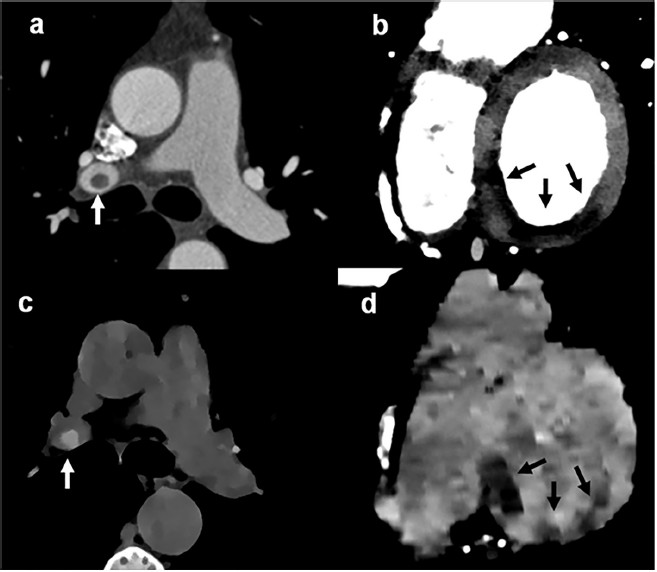

Se efectuó un ecocardiograma transtorácico, que indicó función global ventricular izquierda preservada (fracción de eyección ventricular izquierda 58%) con hipocinesia inferior e inferolateral. Se solicitó una TC (Escáner IQon Spectral, Philips Healthcare, Países Bajos) para descartar un origen embólico (Figura 1). Las imágenes realzadas mediante contraste identificaron la presencia de tromboembolismo pulmonar (Figura 1, panel a, flecha) y un marcado defecto de perfusión de la pared ventricular izquierda basal inferior (Figura 1, panel b, flechas). Se detectó un stent permeable en la arteria circunfleja izquierda, a la vez que se identificó una lesión irregular grave en la arteria coronaria derecha (grande y dominante) distal (Figura 2). Es de destacar que utilizando imágenes de DE, el score de calcio coronario sin contraste (colimación 32 × 0,625, espesor 2,5 mm, 120 kV, 80 mAs, velocidad de rotación 0,33 segundos, gatillado al 75% del intervalo RR), permitió detectar tanto el tromboembolismo pulmonar

(Figura 1, panel c, flecha) como el infarto de miocardio basal inferior (Figura 1, panel d, flechas). El valor de DE medido en el área de alta densidad correspondiente al trombo pulmonar fue de 107,8 % EDW (porcentaje medio de DE relativo al agua), en comparación con valores de 104, 3 % EDW en el tronco de la arteria pulmonar y de 103,9 % EDW en la aorta ascendente. El valor de DE medido en el área de baja densidad correspondiente al infarto de miocardio fue de 101,9 %EDW, en comparación con valores de 104 % EDW en el miocardio remoto.